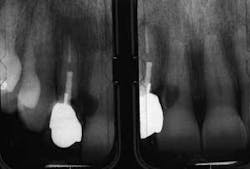

The first patient (see Image 1) was a 63-year-old, white female with no significant medical history. She presented with a buccal abscess between the maxillary right lateral and central incisors. Radiographically, there was evidence of a fracture and decay on the lateral and resorption on the central (see Image 2).

Both teeth were deemed hopeless and slated for extraction. Provisionalization was a challenge as the patient declined wearing a removable appliance, and the adjacent virgin teeth would have required preparation to support a fixed provisional. We elected to extract the teeth, place immediate implants with a narrow-diameter implant in the lateral position (see Image 3), graft between the implant and the extraction site, and place two prefabricated zirconia abutments, which were tightened to 35 Ncm (see Image 4).

The majority of the abutment preparation was performed extraorally. The provisional was relined and luted with a semi-permanent cement (Durelon). Centric and excursive contacts were removed. The patient was advised to adhere to a soft diet and avoid forces to the surgical site. When comparing the patient at the completion of the procedure (see Image 5) and six weeks postoperatively (see Image 6), the soft-tissue levels were maintained. The impression for the final prostheses was made six months following implant placement. Two single Procera AllCeram (Nobel Biocare AB) crowns were then fabricated.